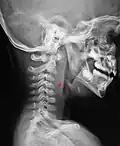

L'espace rétropharyngien est un espace anatomique médian situé entre la paroi postérieure du pharynx et la colonne vertébrale recouverte des muscles prévertébraux et de la lame prévertébrale du fascia cervical.

L'espace rétropharyngien est limité en haut par la partie basilaire de l'os occipital et se prolonge à sa base par le médiastin à partir de la fourchette sternale.

Latéralement, il est limité par la lame sagittale qui le sépare de l'espace latéro-pharyngien et de la gaine carotidienne.